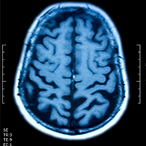

What's the difference between dementia and Alzheimer's?

Dementia is a syndrome — a group of symptoms, not a disease. Alzheimer's is a degenerative brain disease and the most common cause of dementia. We have answers to your questions about Alzheimer's and dementia.